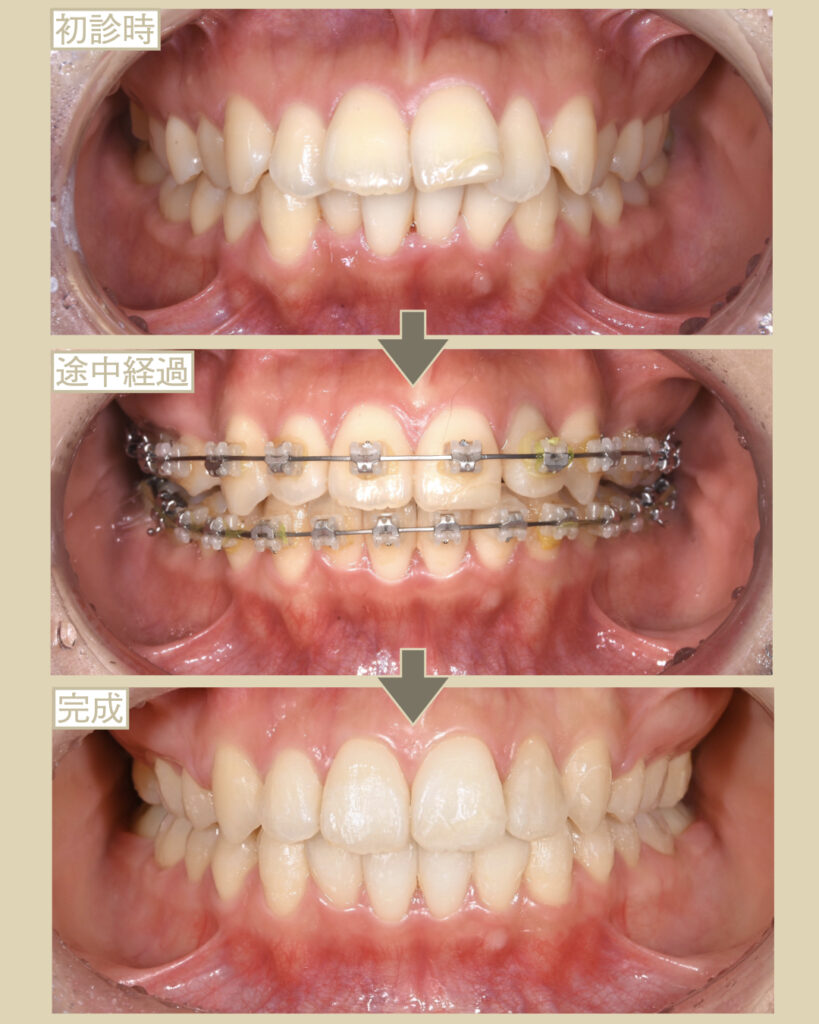

- 主訴:前歯が出ているのが気になる

- 抜歯:あり

- 装置:表側ワイヤー矯正

- 期間:2年半

- 費用:100万円(税別)+調整量月5,000円

上顎左右4番目の歯を抜歯して、歯の移動スペースを確保する。

ワイヤー矯正は、前歯群と奥歯群の引っ張り合いで綺麗なアーチ状にしていきますが…

今回は、出っ歯の症例のため、奥歯群が前に引っ張られないようにゴム掛けを工夫してなるべく前歯だけを後退。

これにより、抜歯した4番目のスペースを活用して、奥歯群は前に移動させずに前歯群だけを後ろへと移動させて、大幅に出っ歯を改善させていきます。

問題点のかみあわせも全体で噛めるようになり、歯の健康寿命が増進しました。

また、出っ歯の改善による虫歯や歯周病のリスクを軽減させ、

口元が引っ込んだ事Eラインができ、相乗的に鼻が高く見えて顎先も出ることで、凹凸のある美しい横顔になりました。

また、梅干しあごの改善と唇を自然に閉じることができました。